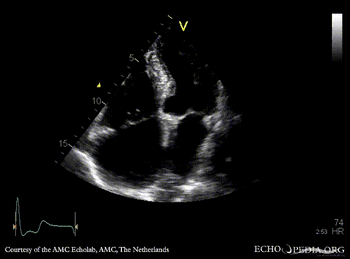

Severe aortic valve stenosis and plaque in abdominal aorta

PLAX: concentric hypertrophy of left ventricle, thickend aortic valve PSAX: concentric hypertrophy of left ventricle